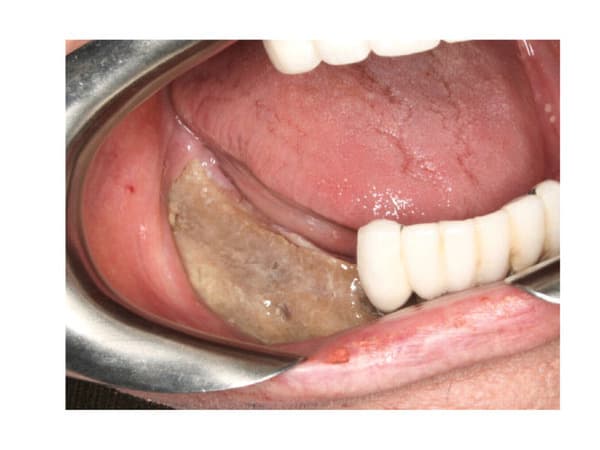

C'est une décision de toute façon terrible à prendre si ATCD de BP en IV, parce que si le surfaçage n'est pas fait et que le terrain paro condamne alors les dents à être extraites, cela risque d'être bien pire pour le patient. Pour le moment, il n'y a semble-t-il aucune solution pour un cas d'osteonecrose, c'est juste un cauchemar...

(image tirée de http://www.nature.com/bonekey/knowledgeenvironment/2011/1103/bonekey20110500/full/bonekey20110500.html )